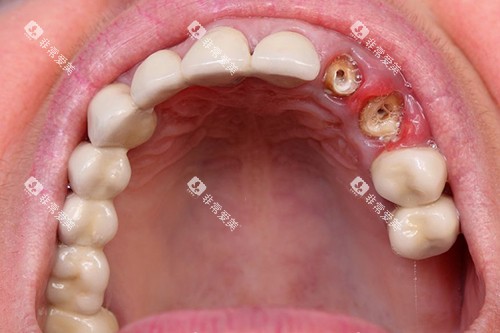

例如,在种植牙领域,拜博口腔采用了即刻种植、小创口种植等较高技术,大大缩短了患者的治疗周期,减少了患者的痛苦。

诺贝尔口腔在种植牙领域具有显著的优势。

医院与国内外老牌的种植牙品牌合作,引进了较高的种植牙系统。

诺贝尔口腔的医生团队在种植牙方面有着丰富的经验和过关的技术。

他们能够根据患者的牙槽骨情况和口腔条件,选择合适的种植体,并进行精密的种植手术。

手术过程中,医生会采用小创口技术,减少患者的创伤和痛苦,提高种植成功几率。